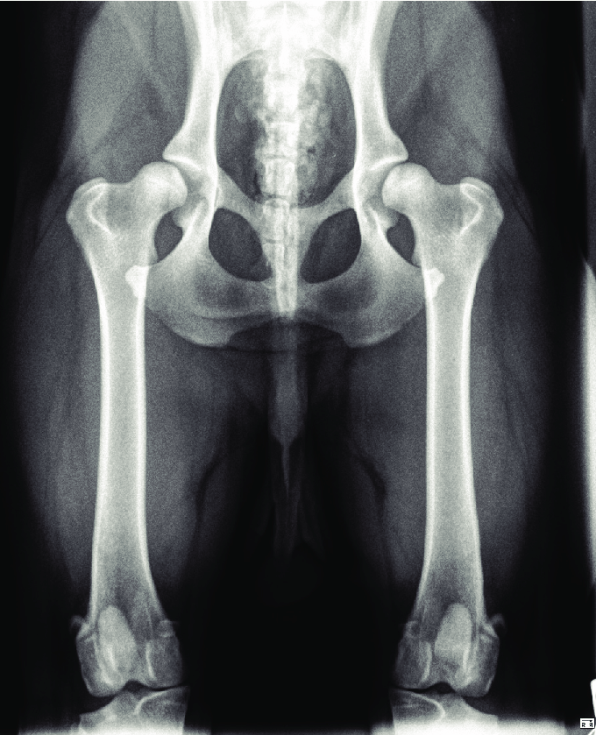

Dépistage de la dysplasie de hanches

Dysplasie des hanches

Explications et point sur les denieres avancées en connaissances des origines, mécanismes, et traitements de la pathologie. Article du Dr Jean-Marc Wurtz, 2022.